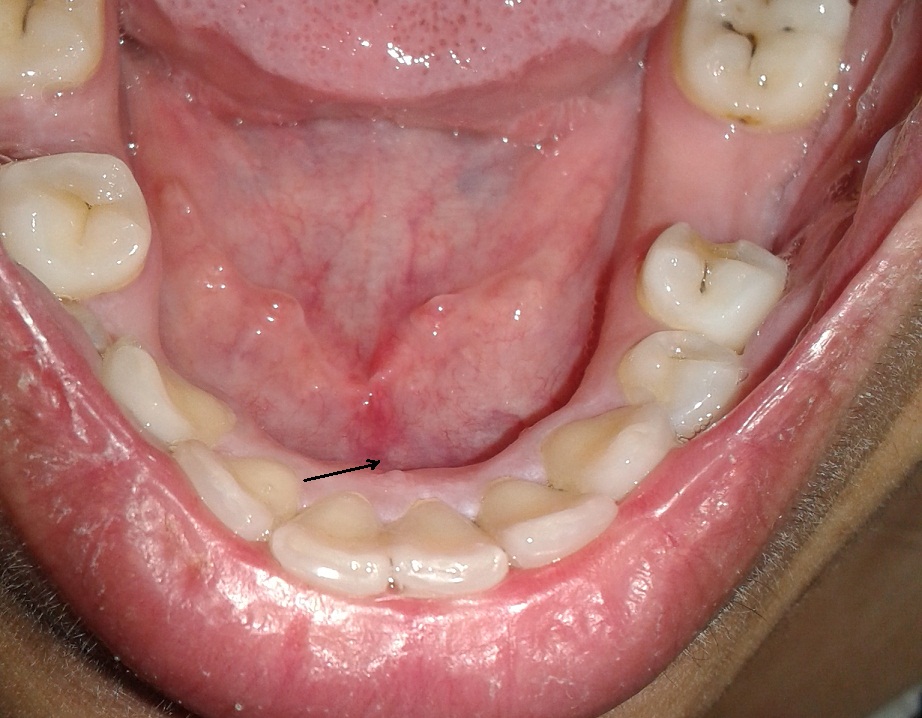

I don't remember how long its been there but at least its been a few months since I've been feeling a small hard immovable lump on the floor of mouth against jaw bone. Its hardly visible but can be felt with tongue and by pressing against it. It wasn't painful until recently when I started touching it more often it feels like ulcerated and is slightly painful sometimes only. Reading articles on google and viewing images is nerve-shattering. Does this need x-ray or biopsy? Can anyone suggest something.

Asa it needs an X-ray to see if it’s a stone of a salivary gland ( spit producing glam) and needs to be seen in the clinic. Might have to be removed for biopsy